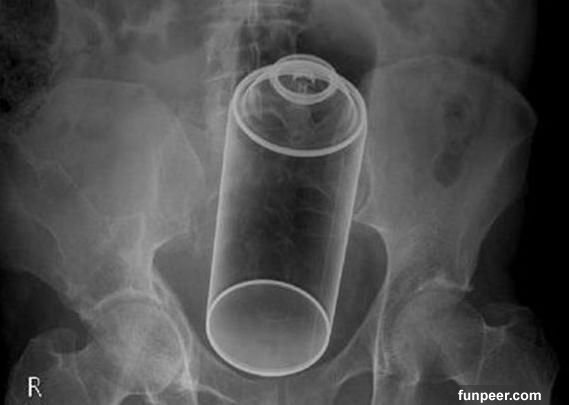

有些人以為,到性用品店買個性工具總不會有危險了吧?錯!使用性用品也可能會出意外的。看看上面這兩個X光片,可憐的使用者居然把震動棒和假陰莖“安家”在體內了。所以提醒各位有意使用性工具的網友:1.購買性工具一定不能貪便宜,要購買品質信得過的;2.使用時要嚴格遵照使用說明,千萬不能隨心所欲;3.正規廠家的產品也難免會有某些出現意外,所以使用前要嚴格檢查它是否安全。

以上圖片這樣的自慰工具,真是令人大吃一驚。可美國有些所謂的“新潮”人,為了尋找刺激,想盡一切辦法尋找最“另類”的自慰工具。後果怎樣呢?看看X光片就知道了——得不償失!

【猜一猜】你能從這些X光片中看出他/她們使用的是什麼東西進行自慰嗎?